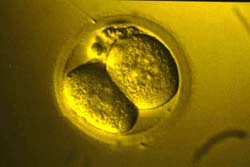

Первые сутки после зачатия. У яйцеклетки уже две дочери.

Вторые сутки после зачатия. Деление продолжается.